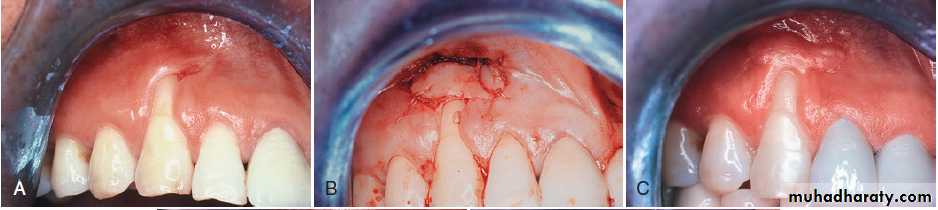

(A) Pretreatment recession defect of 3 mm to be treated with enamel matrix derivative (EMD). (B) Application of EMD to the root surface before coronally advancing the flap with 5-0 plain gut sutures. (C) The 1-year follow-up reveals 100% root coverage and increased keratinized gingiva.